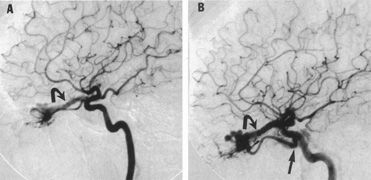

The detection of intracranial AVMs is facilitated by CT scanning and MRI (Fig. 10),88 but optimal management requires selective angiography89 that assesses the size and configuration of the mass, the number and location of feeding arteries, the flow characteristics and degree of steal from brain parenchyma, and the pattern of venous drainage.

Fig. 10. Neuroimaging of arteriovenous malformation. A: Coronal magnetic resonance imaging (MRI) (TR, 600 ms; TE, 20 ms) shows wedge-shaped vascular mass extending from the surface of the parietal cortex (white arrows) to the lateral ventricle (black arrows; asterisk, arterial feeder). B: Posteroanterior left arteriogram of the same lesion. C: Axial computed tomography scan with contrast enhancement. D: Axial MRI of a large arteriovenous malformation, first echo (TR, 2000 ms; TE, 20 ms). E: Second echo (TR, 2000 ms; TE, 90 ms). (From Smith HJ, Strother CM, Kikuchi Y, et al: MR imaging in the management of supratentorial intracranial AVMS. AJNR Am J Neuroradiol 9:225, 1988.)